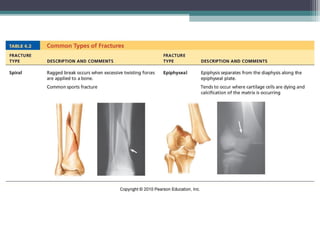

Fractures (Breaks)

Classified by:

1.Position of bone – nondisplaced (normal) or

displaced (bone out of alignment)

2.Completeness of break – complete (broken

through) or incomplete

3.Orientation to long axis of bone – linear

(parallel to bone) or transverse (perpendicular to

bone)

4.If bone penetrates skin – open (compound)

fracture or closed (simple) fracture

Fractures (Breaks) Classified by: 1.Positionof bone – nondisplaced (normal) or displaced (bone out of alignment) 2.Completeness of break – complete (broken through) or incomplete 3.Orientation to long axis of bone – linear (parallel to bone) or transverse (perpendicular to bone) 4.If bone penetrates skin – open (compound) fracture or closed (simple) fracture